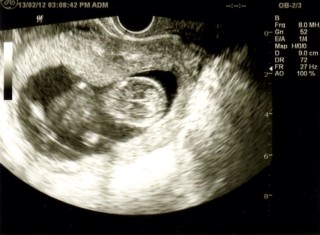

12w5d/CRL68.8mm

前回までは手足の動きはぱたぱたとした感じだけだったのに、股関節と膝関節を使って脚を曲げたり伸ばしたりしていました。

まだ胎動は感じないけど、すくすく育ってるなぁと実感しました。